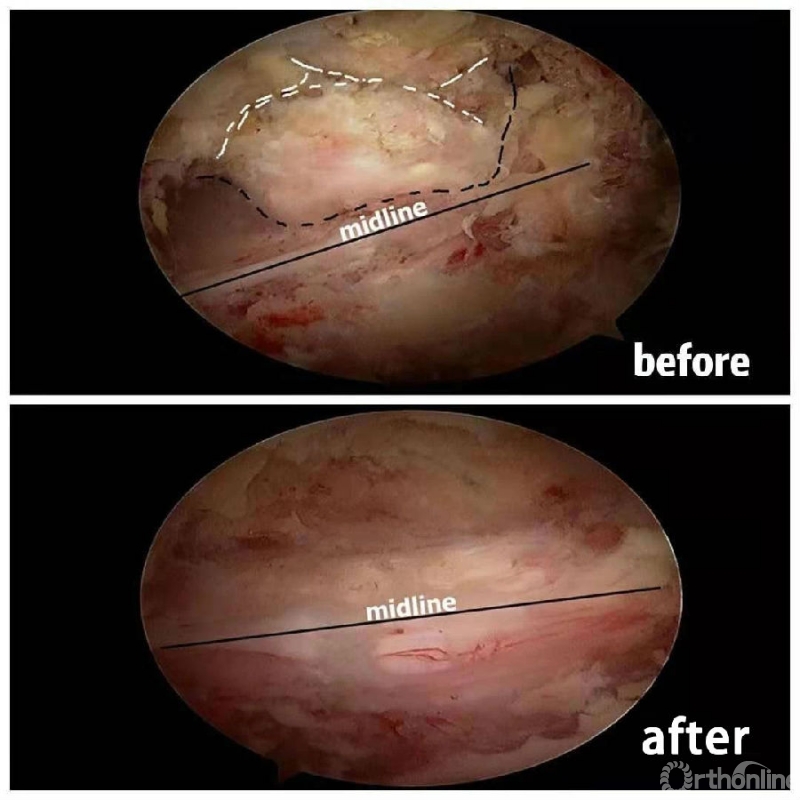

3.从游离骨块的背侧开始,用磨钻将骨块打薄,然后将骨块的底面与脊髓表面仔细分离,将游离骨块摘除;

4.进一步加深移除骨赘的残余部分,直到显露出对侧的神经根及关节突关节的内壁;

术中操作要点

1. 术中如何确定中线?

2. 术中骨赘的界限?

3. 如何确定对侧结构?

4. 如何确定减压范围?

5. 减压完成后的止血非常重要,高效的止血方法有哪些?